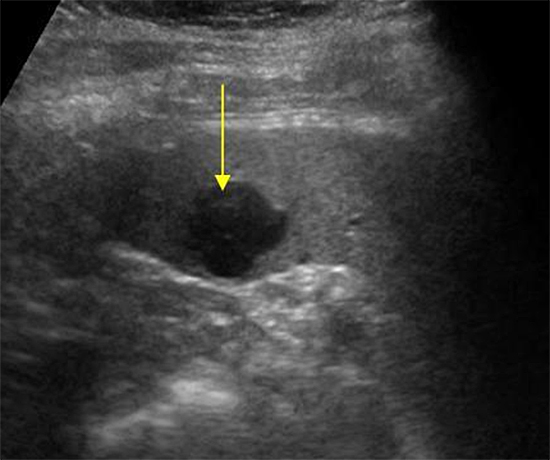

А пока предлагаю вам разгадать вот такую загадку.

Как вы думаете:

1. Это жидкостное или мягко тканное образование в селезенке?

2. Нужно ли здесь для верификации образования использовать цветной допплер или нет?